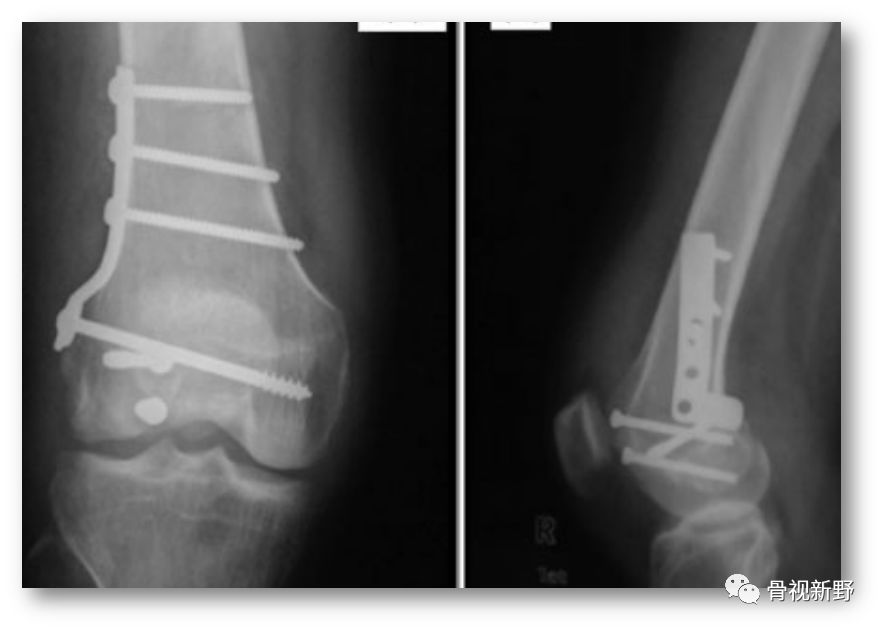

钢板-螺钉固定

在诸多螺钉固定失败的经验教训及在Buttress支理念支持下,各种拉力螺钉+钢板的组合应用均有报道,但总体以小直径拉力螺钉+小钢板支持或保护固定(后方/侧方)为主流趋势:

单纯后方Buttress钢板固定

后内侧单纯钢板螺钉直接Buttress固定

侧方支持/中和钢板

后方Buttress钢板固定

大直径拉力螺钉+重建板后内侧Buttress

无头加压螺钉(PA/AP)+重建板后内侧Buttress

后方+侧方双钢板固定

小直径拉力螺钉+1/3管型钢板(扭转)后外侧Buttress+外侧LCP中和钢板

小直径拉力螺钉+侧方支持钢板+后方Buttress重建钢板

小直径拉力螺钉+LCP侧方支持钢板+后方Buttress钢板